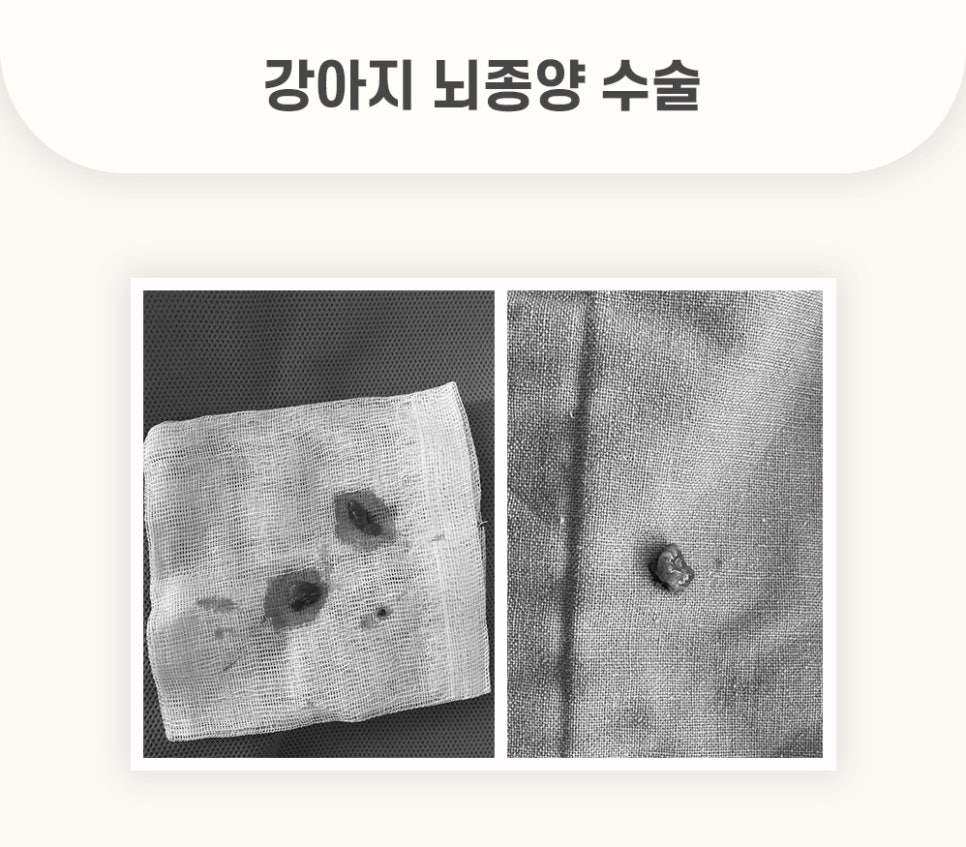

성공적으로 제거된 강아지 뇌 종양입니다. 수술 후 조직검사까지 실행하였습니다.